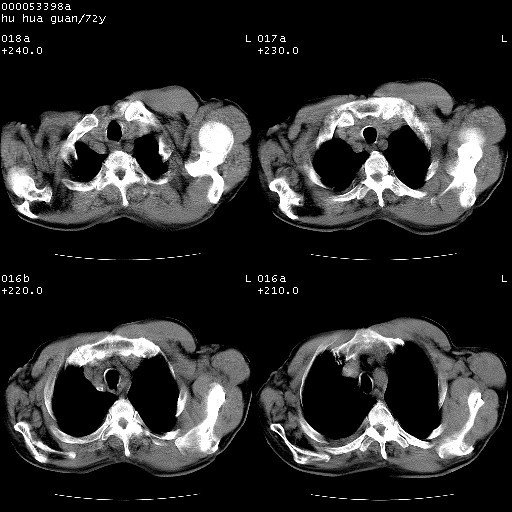

标题: CT15582:M,72Y。请老师帮分析胸部病变。

可以明确的说。肯定不是主动脉夹层破裂出血!考虑为淋巴瘤或间叶组织来源的恶性肿瘤可能性大。右肺小结节建议薄层观察,如能发现恶性征象,那椎前改变就考虑为转移所致。至于双侧少量胸水乃静脉血回流受阻所致。

降主动脉前移位,后纵隔占位

后纵隔占位,降主动脉前移位;双侧胸腔积液;应排外食管病变侵犯血管可能;

建议排除结核引起的冷脓肿。